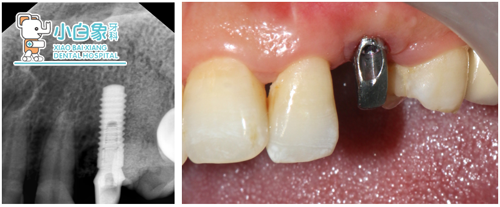

口内像+X线片

治疗过程:23必兰局麻下切开翻瓣,拔除残根,根尖区骨缺损,根尖大量肉芽组织,彻底去除后24根面部分暴露,预备种植窝后植入ITI3.3*12mm骨水平种植体一枚,上愈合帽后填塞Bio-oss骨粉,海奥膜覆盖,严密缝合。

残根

植入后X线片